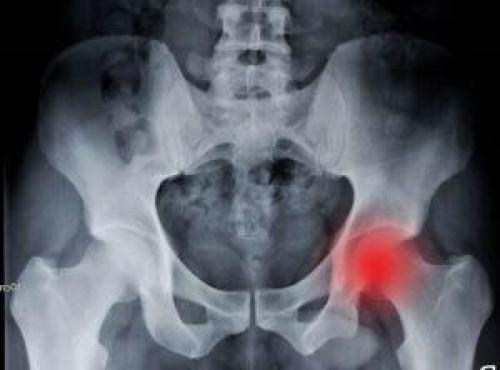

Коксартроз тазобедренного сустава 3 степени. Консервативное лечение или операция

Коксартроз (артроз тазобедренного сустава) 3 степени – стадия заболевания, когда происходят выраженные, необратимые изменения:

- Почти исчезает суставная щель.

- Хрящевая поверхность разрушена.

- Вертлужная впадина и головка тазобедренной кости становятся плоскими, увеличиваются в размерах из-за костных разрастаний по краям.

- Сустав сильно деформирован.

Тазобедренный сустав, деформированный при заболевании

Человек с коксартрозом тазобедренного сустава 3 степени испытывает постоянные и сильные боли в бедре. При этом мышцы утрачивают силу и объем, походка становится прихрамывающей, переваливающейся, «утиной». Из-за деформации суставов нога к 3 стадии может укоротиться на 10–15 см.

Во время движения все чаще происходит отслоение кусочков хряща, которое провоцирует воспаление синовиальной оболочки и обострение коксартроза. Капсула к этому времени становится неэластичной. Также она утолщается из-за повторяющегося воспаления.

Лечение артроза тазобедренного сустава без операции на этом этапе – всего лишь способ задержать его полное разрушение. Вернуть ему функции и привычную форму можно только хирургическим путем.